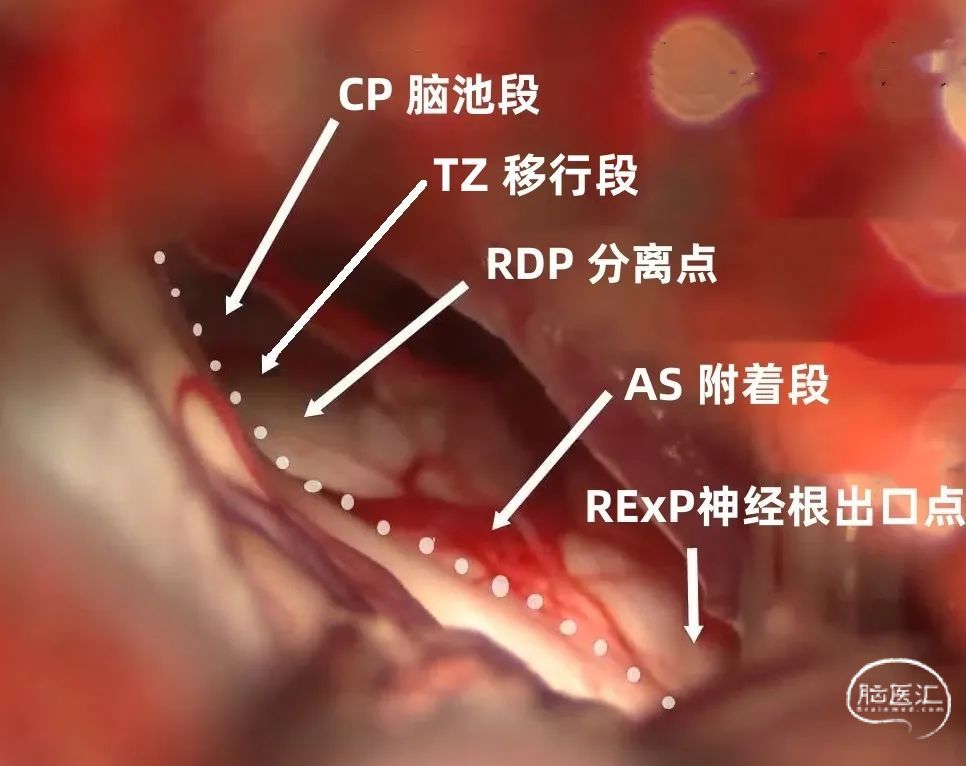

Campos-Benitez等将面神经根出脑干区分为(下图):

面神经根出桥延沟的点(root exit point, RExP, 神经根出口点)

面神经在脑桥表面的附着段(attached segment,AS,附着段)

面神经离开脑桥点(root detachment point, RDP, 分离点)

移行段(transitional zone, TZ, 移行段)

面神经REZ区位于面神经中枢端与外周端交界处并且髓鞘薄弱,受到责任血管压迫后容易发生脱髓鞘改变。责任动脉的扩张和延长是导致动脉压迫神经的重要原因。